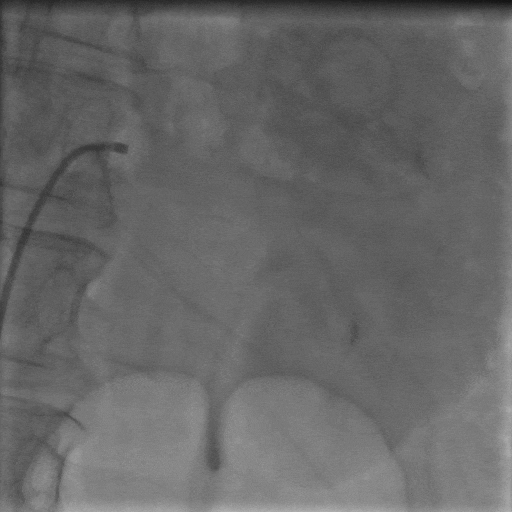

手術(shù)中,團(tuán)隊(duì)通過(guò)穿刺右側(cè)股動(dòng)脈,置入動(dòng)脈鞘和導(dǎo)管,對(duì)左右腎動(dòng)脈進(jìn)行造影評(píng)估后,使用Hawk Sonic超聲消融導(dǎo)管對(duì)腎動(dòng)脈分支及主干進(jìn)行消融治療。

術(shù)后患者血壓顯著下降,復(fù)測(cè)血壓149/72mmHg;手術(shù)次日血壓降至122/66mmHg,且術(shù)后2個(gè)月未發(fā)生任何不良事件,復(fù)查腎動(dòng)脈CTA未見(jiàn)狹窄等異常。

▲左側(cè)腎動(dòng)脈造影